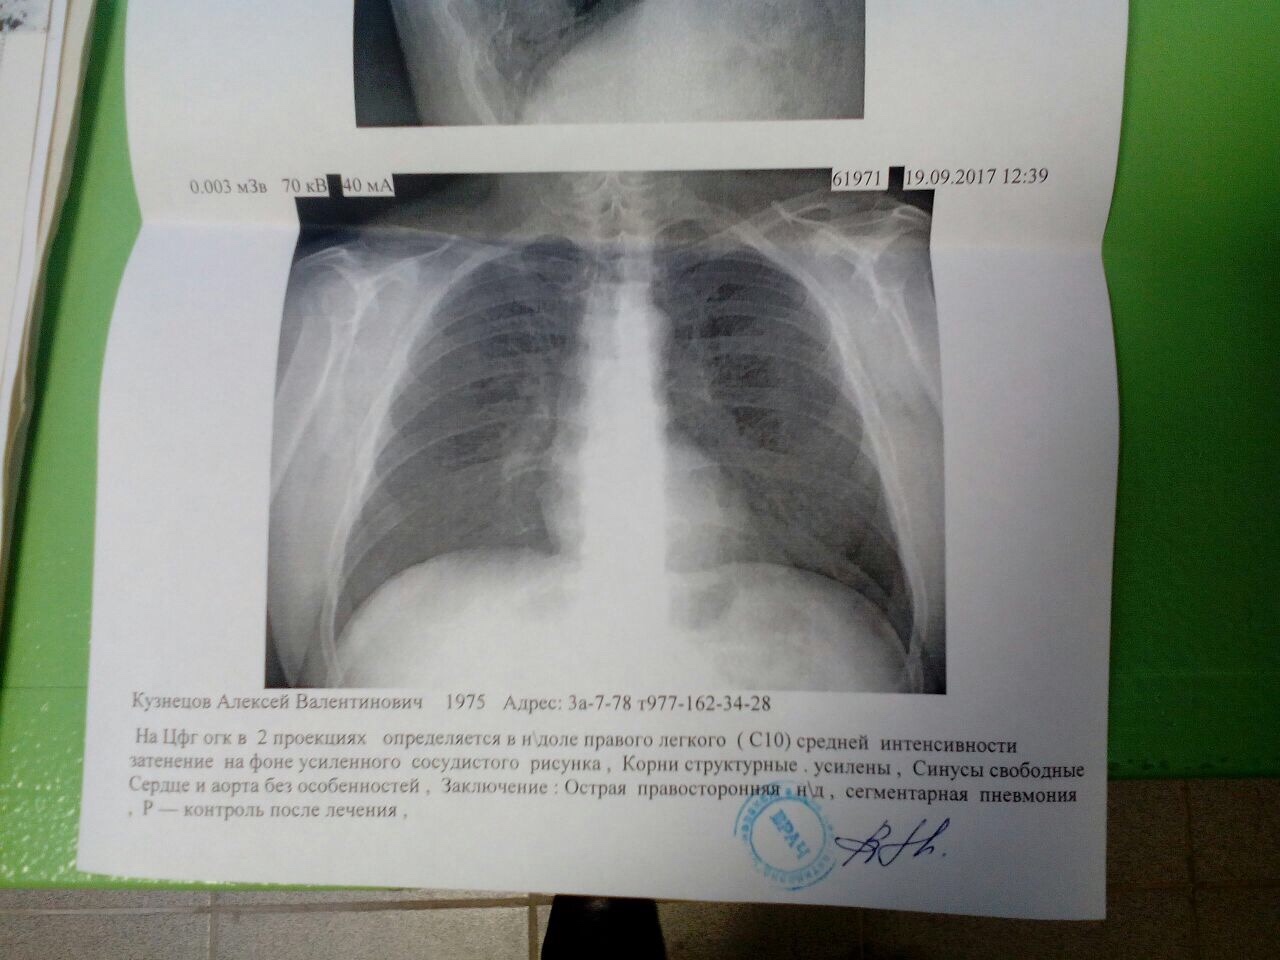

Рентгенодиагностика бронхопневмонии: Советы и примеры

Раздел: Альбом открытий